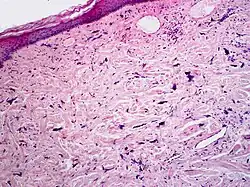

Pleomorphic fibromas of the skin usually present in adults, with a slight preponderance in women.[1]